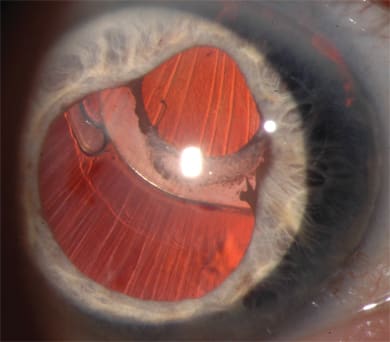

The configuration of the optic-haptic junction may contribute to IOL decentration (Figure 3), thus interfering with the examination and treatment of vitreoretinal diseases. Plate-haptic construction has largely fallen out of favor due to a higher rate of IOL dislocation, both spontaneously and following YAG laser capsulotomy.38-44 This higher rate of dislocation may be due to poor capsular fixation and increased posterior bowing. The silicone plate-haptic IOL is particularly susceptible to the forces of capsular contraction. Silicone does not adhere well to the capsule, and compression produces folding or buckling out of the plane of the IOL rather than compression within the plane, as with a loop-design IOL.45 Studies have not shown significant differences between single and multipiece IOLs with regards to tilt, decentration, or capsular contraction following implantation in an intact capsular bag.46,47

Figure 2. Capsular instability leading to marked superonasal decentration of a single-piece hydrophobic posterior chamber intraocular lens.